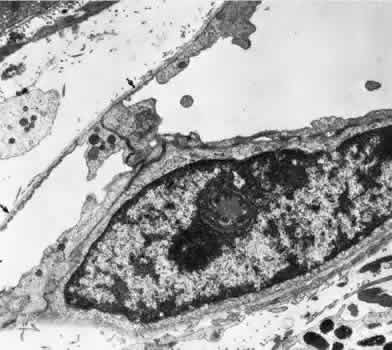

Retinal capillaries range in diameter from 4 to6 μm. The capillaries throughout the retina, including those of the radial peripapillary network, have the same fine structure.23 The capillary wall consists of a continuous layer of flattened and longitudinally oriented endothelial cells and an incomplete layer of longitudinally oriented pericytes (Fig. 8). The pericytes (formerly referred to as mural cells) are closely spaced, resulting in an approximate ratio of pericytes to endothelial cells of 1:1, a relatively high ratio compared with elsewhere in the central nervous system.

Fig. 8. An electron micrograph of a human retinal capillary. An incomplete layer of pericytes (P) is present. Glial cells make direct contact with the basement membrane (arrows) surrounding the endothelial cells (E).

Ultrastructural examination of the endothelial cells of retinal capillaries shows that the cytoplasm of the cell bulges in the region of the nucleus. This area contains the Golgi apparatus, centrioles, and rough-surfaced endoplasmic reticulum. The remainder of the cytoplasm contains moderate amounts of smooth endoplasmic reticulum and mitochondria. The average endothelial cell thickness is 236 nm.

Pinocytotic vesicles occur in the cells of the retinal capillaries. The vesicles are of uniform size, with an average diameter of 70 nm. Pinocytotic vesicles are found on the lumen (10% of total) and basement membrane (28%) side of the endothelial cells and free in the cytoplasm (62%). Approximately 2% of the volume of the endothelial cell is occupied by pinocytotic vesicles, a number that is substantially lower than that of other continuous capillaries. Pinocytotic vesicles of similar morphology and location are found in pericytes, but not in any number on glial cell membranes. Animal experimental evidence shows that these vesicles may be responsible for transporting substances from the vitreous cavity into the retinal vasculature in a unidirectional fashion.24

In the region of the endothelial cell junctions, cytoplasmic processes may overlap and form flap-like extensions that project into the lumen. The outer leaflets of adjacent endothelial membranes form very tight occluding junctions. The basement membrane surrounding the endothelial cell is well developed and continuous with the basement membrane surrounding the pericytes. The basement membrane of the retinal capillaries is structurally similar to that of the retinal arteries and veins in that collagen types 4 and 5, laminin, and heparin sulfate proteoglycan core protein are prominent features. Collagen types 1 and 2 appear to be lacking.12 Some areas show thinning of the basement membrane, and in these regions the endothelial cells and pericytes are closely apposed. Specifically, the capillary basement membrane between pericytes and endothelial cells is much thinner than the basement membrane covering the two types of cells.25 This arrangement probably allows increased communications between the cells. The retinal capillary basement membrane is thicker than in most other capillaries in the body, and in certain disease states such as diabetes, this thickness increases further.26

The pericytes of the retinal capillaries are not as elongated as the endothelial cells. They are endowed with multiple arm-like processes that wrap around the surrounding endothelial cells. Pericyte processes appear to cover about 85% of the entire circumference of the available capillary endothelial tube.25 Pinocytotic vesicles can be seen near the adventitial (outer) side of the cell body. In the peripheral retina, the retinal glial cells are in direct contact with the basement membrane surrounding the pericytes. Evidence suggests that the retinal pericytes are directly involved in the local control of retinal blood flow (RBF) and may affect endothelial proliferation as well.25